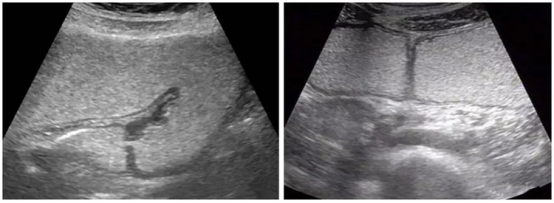

超声正常胃肠图像▲